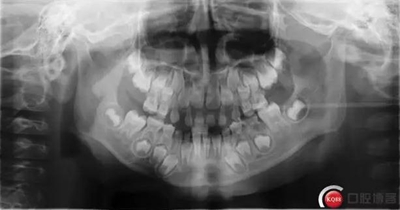

檢查:*75殘冠穿通髓腔,質(zhì)軟,叩診(++),溫度測試無反應(yīng),X線顯示遠(yuǎn)中根已完全吸收、近中根吸收至根頸1/3,且根尖可見低密度暗影。

診斷:*75牙體缺損+根尖周炎

2.jpg